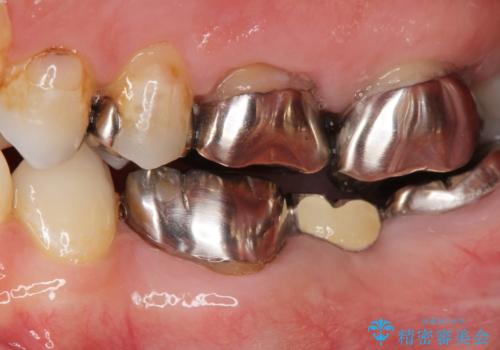

[フルジルコニアクラウン] 老朽化した銀歯を白く